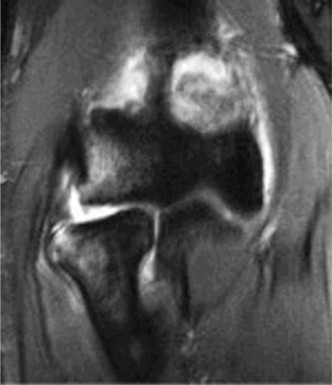

A 31-year-old male is seen in the emergency room after sustaining a knee injury. He reports he was playing pi…